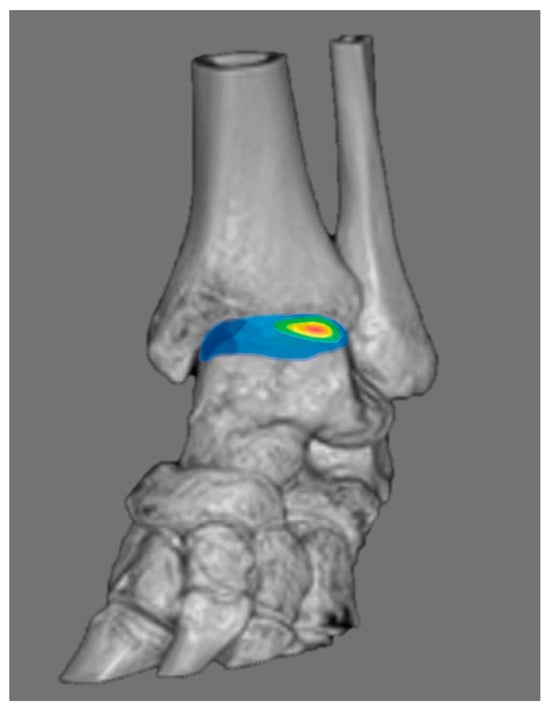

3.4. Chronic Ankle Instability